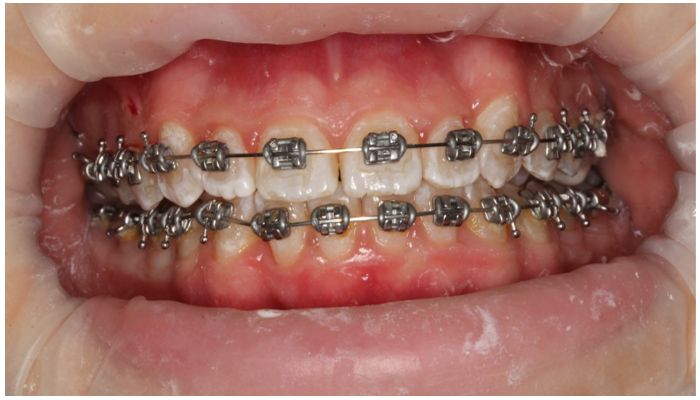

Ортопедические методы при сформировавшейся прогнатии практически не имеют силы. Только у небольшого числа пациентов можно замаскировать прогнатию удалением отдельных моляров и длительным ношением брекетовых системам.